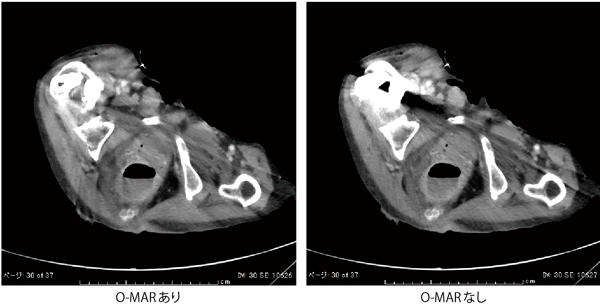

同センターでは,フィリップスの金属アーチファクトを低減する再構成技術であるO-MAR(Metal Artifact Reduction for Orthopedic Implant)を導入し,整形外科の人工股関節が留置された患者さんへの撮影などに活用している。O-MARは,独自のアルゴリズムによって整形用の金属インプラントのアーチファクトを補正する逐次近似再構成を応用した技術で,チェックボックスをクリックするだけで使用でき,撮影後にraw dataを元に適用することも可能だ。データとしては,オリジナル画像とO-MAR適用画像の2種類が作成され,両画像を比較して観察することが推奨されている。

検査におけるO-MARの運用について,佐田技師は次のように説明する。

「整形外科領域ではもちろんのこと,大腿骨骨頭置換術によって人工股関節のようなインプラントが入っている患者さんに対して,検査時にO-MARを適用することで金属アーチファクトが除去され,関節周囲や膀胱,前立腺などの軟部組織の観察がある程度可能になります。画面上でO-MAR適用のチェックを入れるだけで,自動的に処理画像とオリジナル画像が生成されますので,検査の際に特に手をかける必要はありません」

O-MARの効果について中浦部長は,「これまでCTでは,金属によるアーチファクトの影響を除去することはあきらめていましたが,O-MARによって,これまで観察できなかった人工関節周囲の構造や軟部組織などが見えてくる可能性があると感じています。一方で,被検者によって効果の程度に差があるため,読影の際にはオリジナル画像と比較参照することが重要です。その意味で,O-MARは従来なかった素晴らしい“補助ツール”であると言えると思います」と述べる。

同センターでは,整形外科で大腿骨骨頭置換術を数多く手掛けており,O-MARによる術後のフォローアップ撮影を週4~5件行っている。佐田技師は,「画像の評価方法や画質の検討はまだこれから行っていく必要があると思いますが,O-MARは,インプラントのある患者さんの画像診断において有効なツールとなっていくことは間違いないでしょう。整形外科医からも喜ばれています」と評価する。

●O-MAR(Metal Artifact Reduction for Orthopedic Implant)による画像比較

O-MAR(Metal Artifact Reduction for Orthopedic Implant)による画像比較